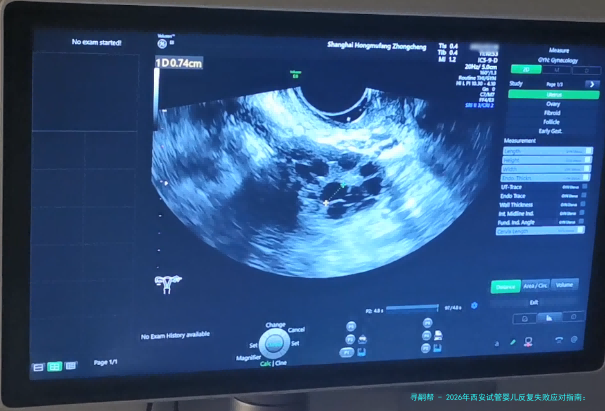

宫腔环境: 通过宫腔镜等检查评介内呈膜样况。